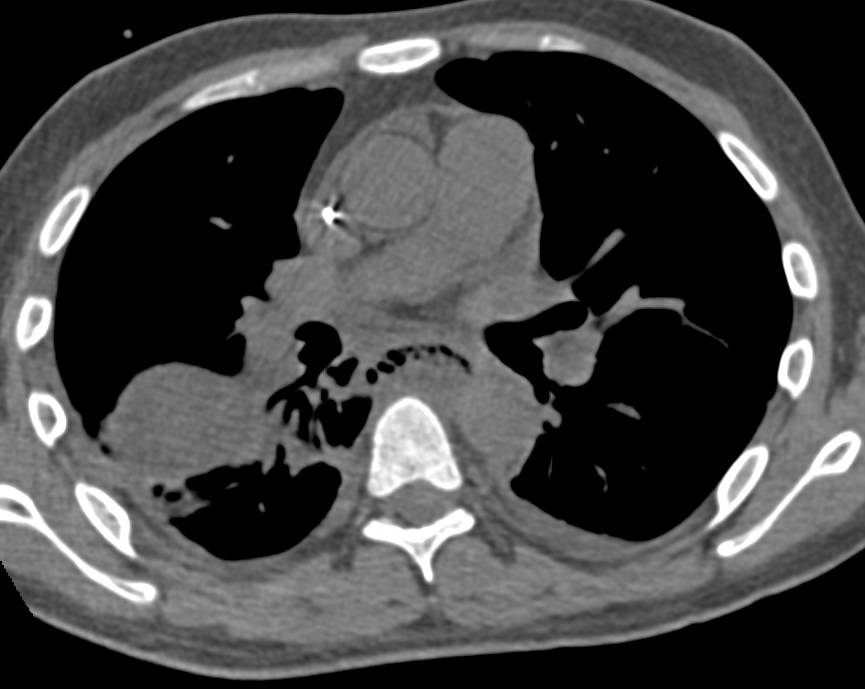

Large Paraesophageal Hiatal Hernia